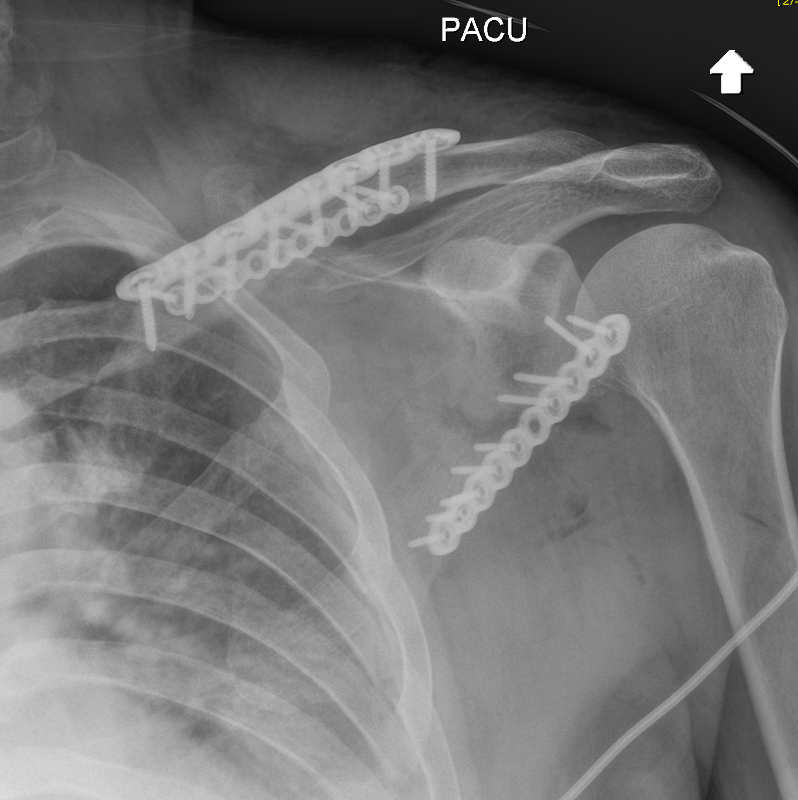

ORIF clavicle

ORIF clavice + scapula

Scapular neck fracture with clavicle fracture